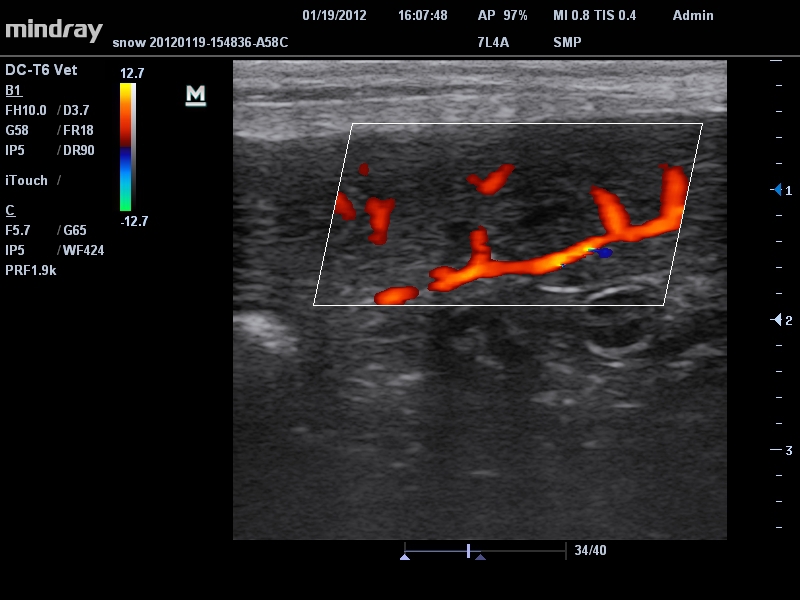

Ветеринария:

Да

• Режимы сканирования: B/M/CFM/PDI/Направленный PDI/PW, HPRF, Тканевая гармоника, М- и цветной М-режим.

• Линейный ультразвуковой датчик Mindray 7L4A